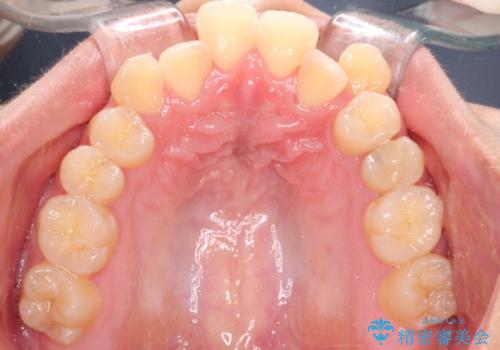

- 八重歯と口元が出ていることを主訴に来院されました。

レントゲンの検査において、前歯も外側に傾いてる結果であったため、上下左右の小臼歯を抜歯して配列を行いました。

歯の動きも良く短期間で治療を終えられたため患者さんにも大変満足していただきました。